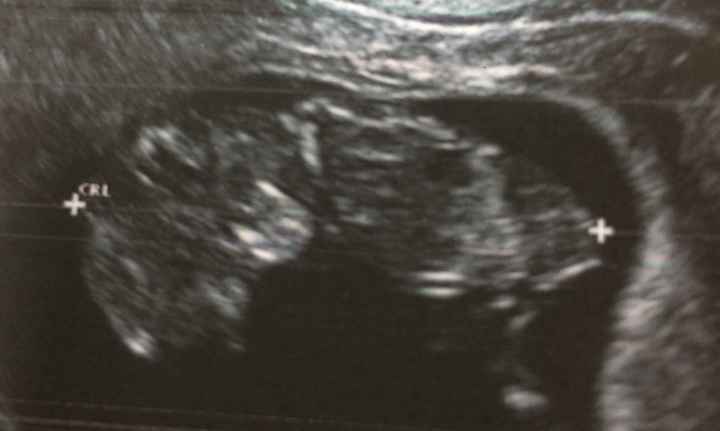

Felicemente sposata con l'uomo di cui mi sono innamorata 12 anni fa e che mi ha regalato la gioia di diventare mamma della nostra piccola Giorgia!